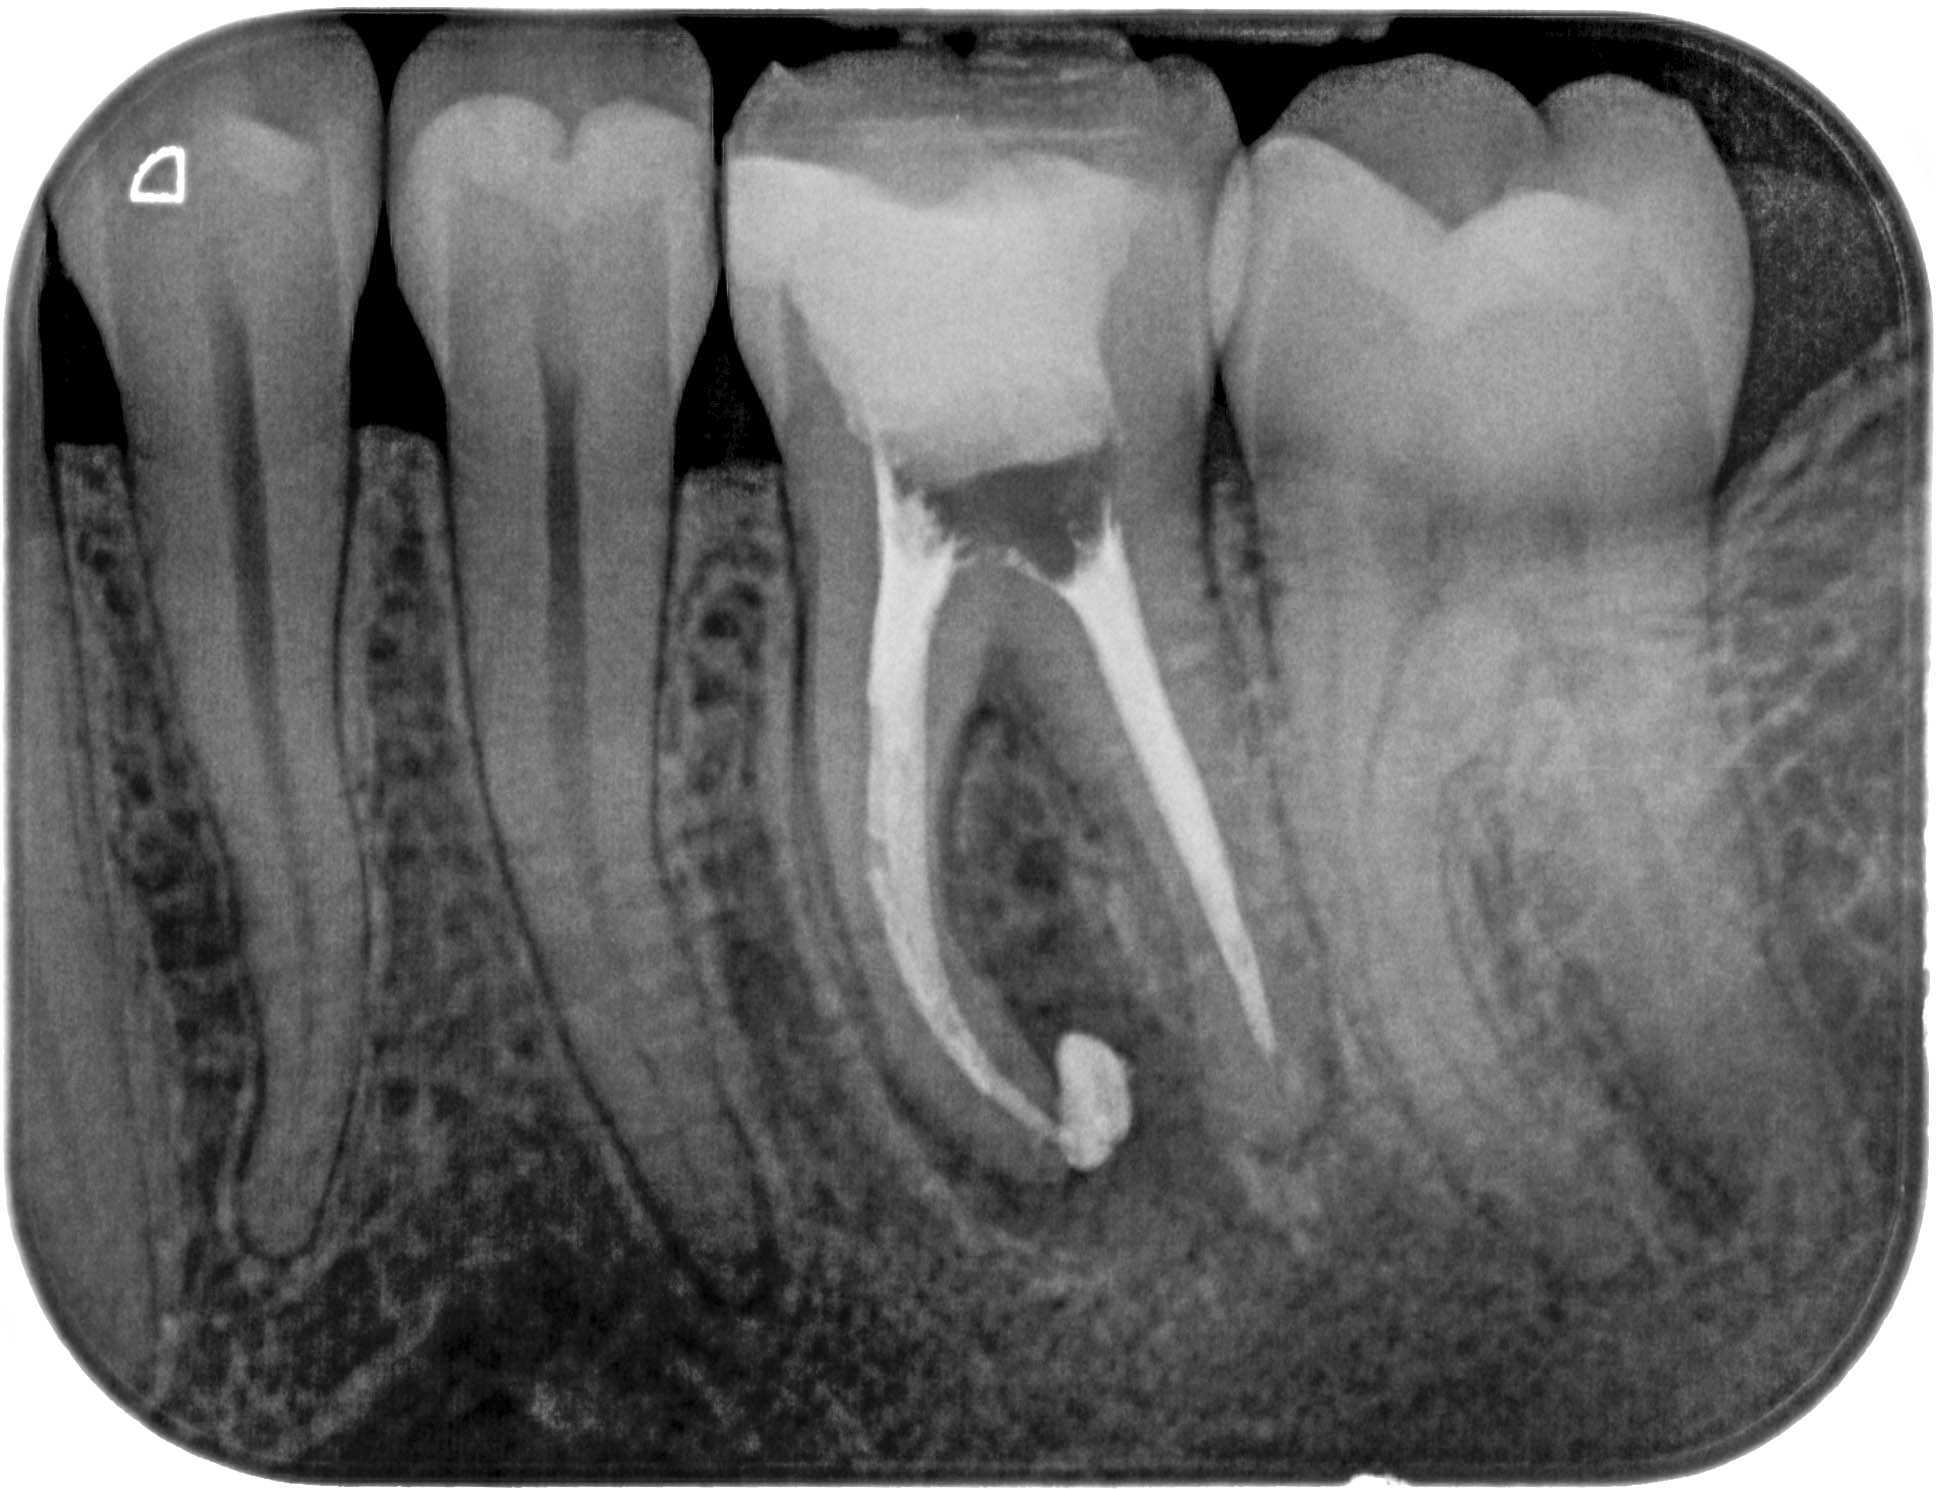

20.03.2012 Veröffentlicht 14. März 2016 am 1936 × 1489 in Calciumhydroxid – Überpressung (1) 20.03.2012